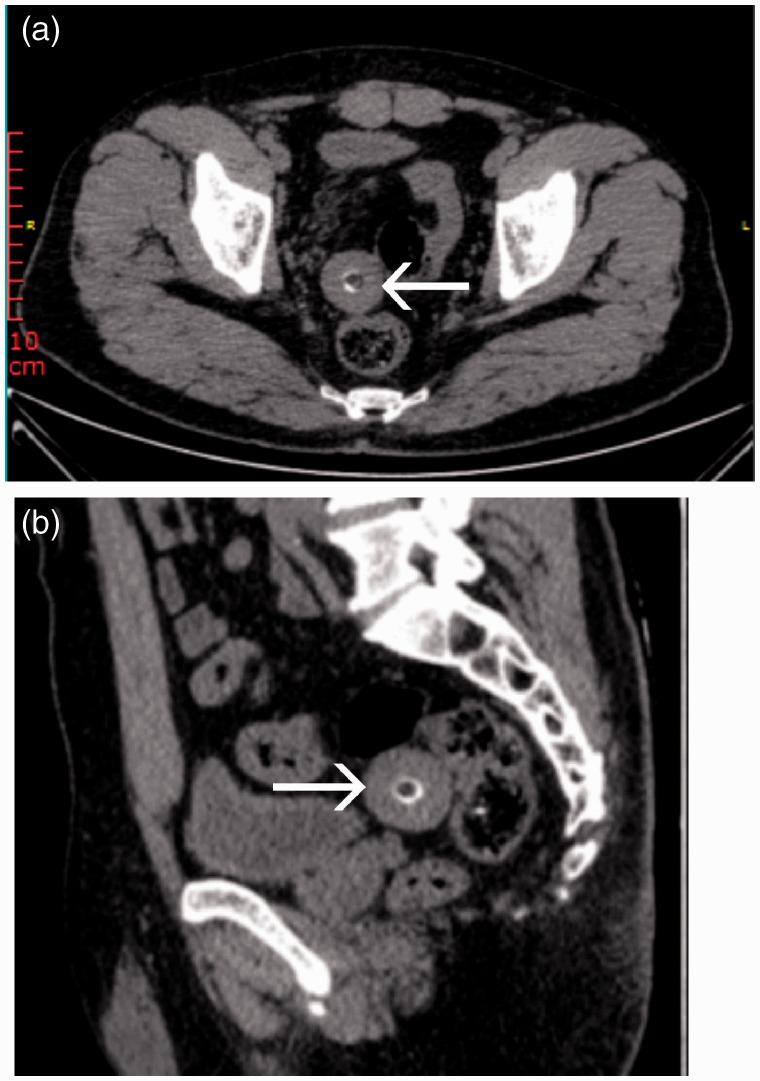

Peritoneal loose body (PLB) is an extremely rare clinical entity, and its preoperative diagnosis is often difficult. We report a case of giant PLB (GPLB) confirmed by exploratory laparoscopy. A 46-year-old man was admitted to hospital with an abdominal mass and urinary frequency. He underwent clinical and laboratory tests and computed tomography (CT), which indicated a lesion at the bottom of the bladder. Exploratory laparoscopic surgery revealed a GPLB, which was subsequently removed. The patient was comfortable after surgery and was discharged 3 days later. His symptoms of frequent urination improved during the 1-month follow-up period. The egg-shaped mass excised from the peritoneal cavity measured 45 × 40 × 33 mm. This case indicates that exploratory laparoscopy can be considered as the first-choice diagnostic procedure for patients with GPLB.

腹膜游离体(PLB)是一种极为罕见的临床实体,其术前诊断往往困难。我们报告一例经腹腔镜探查确诊的巨大腹膜游离体(GPLB)病例。一名46岁男性因腹部肿块和尿频入院。他接受了临床和实验室检查以及计算机断层扫描(CT),结果显示膀胱底部有一个病变。腹腔镜探查手术发现一个GPLB,随后将其切除。患者术后情况良好,3天后出院。在1个月的随访期内,他的尿频症状有所改善。从腹腔切除的椭圆形肿块尺寸为45×40×33mm。该病例表明,腹腔镜探查可被视为GPLB患者的首选诊断方法。